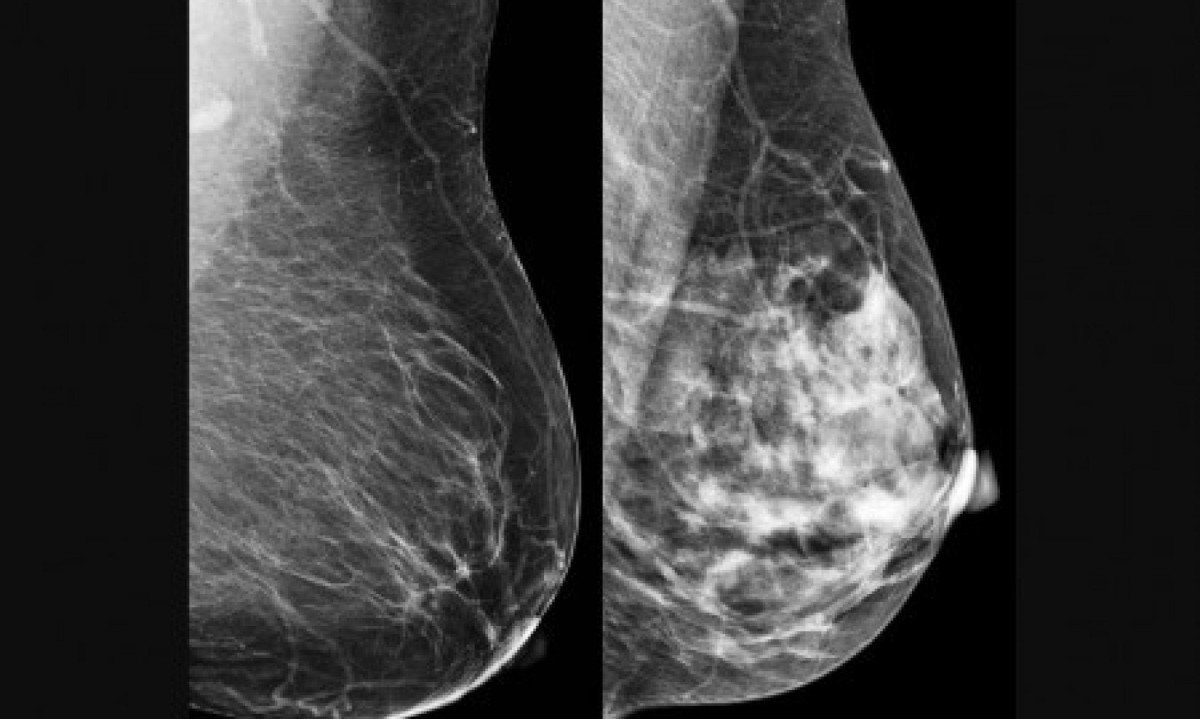

O trabalho foi publicado nos anais do 38º International Symposium on Computer-Based Medical Systems (CBMS), do Institute of Electrical and Electronics Engineers (IEEE). Nele, os autores descrevem uma rede neural híbrida que combina camadas quânticas com camadas clássicas, utilizando uma abordagem conhecida como “quanvolutional neural network” (QNN). O modelo foi aplicado a imagens de mamografias e ultrassonografias com o objetivo de classificar lesões como benignas ou malignas.

O câncer de mama foi escolhido como alvo para teste do modelo computacional porque é o tipo mais comum entre mulheres no mundo, com 2,3 milhões de casos e 670 mil mortes registradas em 2022. A detecção precoce é crucial para aumentar as chances de cura e sobrevida. No entanto, métodos tradicionais, como a mamografia, dependem fortemente da interpretação humana, o que pode levar a variações no diagnóstico. “Apesar de ser teoricamente simples de acompanhar, a mamografia ainda é um exame cuja interpretação depende muito do profissional que realiza o procedimento”, diz Papa.

No estudo, as informações codificadas nos qubits foram pixels das imagens de mamografia e ultrassonografia. Às vezes, um pixel apenas; às vezes, mais de um. O modelo foi testado com duas bases de dados: BreastMNIST (com imagens de ultrassonografia) e BCDR (com mamografias segmentadas). Mesmo utilizando um circuito com apenas quatro qubits, a rede híbrida obteve desempenho competitivo. No melhor caso, alcançou 87,2% de acurácia no conjunto de teste e 86,1% no de validação. “A ideia foi criar uma arquitetura que poderá ser utilizada e aprofundada em outros estudos”, comenta Rodrigues.